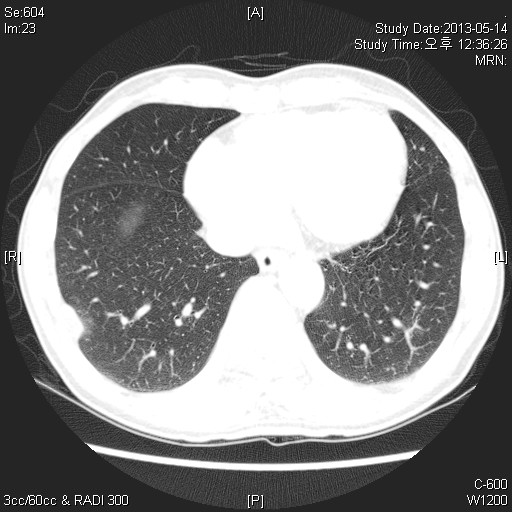

59¼¼ ³²È¯ ƯÀÌ ³»°úÀû °ú°Å·Â ¾ø´ø ȯÀÚ·Î °Ç°­°ËÁøÀ¸·Î ½ÃÇàÇÑ CxR »ó ÀÌ»ó¼Ò°ßº¸¿© refer µÈ ȯÀÚÀÔ´Ï´Ù.

³»¿ø´ç½Ã ƯÀÌ Áõ»ó¾ø¾ú°í,³»¿ø ´ç½Ã lab °ú CxR,chest CT ´Â ´ÙÀ½°ú °°½À´Ï´Ù.